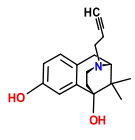

Benzomorphans

- 5,9 alpha-diethyl-2-hydroxybenzomorphan (5,9-DEHB)

- 8-Carboxamidocyclazocine (8-CAC)

- Alazocine

- Anazocine

- Bremazocine

- Butinazocine

- Carbazocine

- Cogazocine

- Cyclazocine

- Dezocine

- Eptazocine

- Etazocine

- Ethylketazocine

- Fedotozine

- Fluorophen

- Gemazocine

- Ibazocine

- Ketazocine

- Metazocine

- Moxazocine

- Pentazocine

- Phenazocine

- Quadazocine

- SKF-10047

Structures

| Benzomorphans | ||||

|---|---|---|---|---|

5,9 alpha-diethyl-2-hydroxybenzomorphan 5,9 alpha-diethyl-2-hydroxybenzomorphan (5,9-DEHB) |

8-Carboxamidocyclazocine 8-Carboxamidocyclazocine |

Alazocine Alazocine |

Anazocine Anazocine |

Bremazocine Bremazocine |

Butinazocine Butinazocine |

Carbazocine Carbazocine |

Cogazocine Cogazocine |

Cyclazocine Cyclazocine |

Dezocine Dezocine |

Eptazocine Eptazocine |

Etazocine Etazocine |

Ethylketocyclazocine Ethylketocyclazocine |

Fedotozine Fedotozine |

Fluorophen Fluorophen |

Gemazocine Gemazocine |

Ibazocine Ibazocine |

Ketazocine Ketazocine |

Metazocine Metazocine |

Moxazocine Moxazocine |

Pentazocine Pentazocine |

Phenazocine Phenazocine |

Quadazocine Quadazocine

|

Thiazocine Thiazocine |

Tonazocine Tonazocine |

Volazocine Volazocine |

Zenazocine Zenazocine |